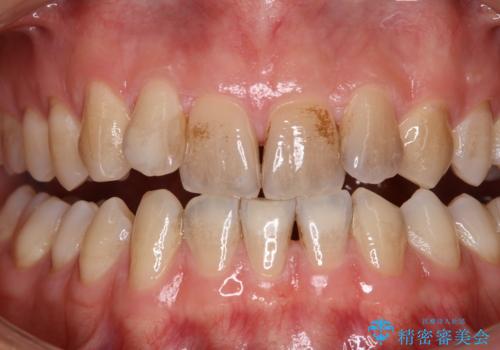

クリーニング(PMTC)掲載症例数554件

最新 クリーニング(PMTC)症例